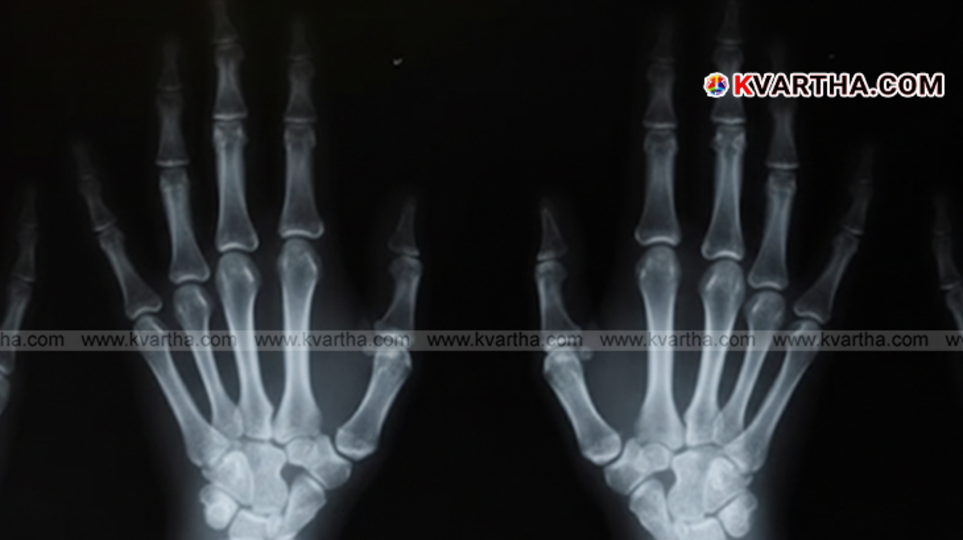

ബീജിംഗ്: (KVARTHA) ഓർത്തോപീഡിക് ചികിത്സാ രംഗത്ത് ഒരു പുതിയ വഴിത്തിരിവായി മാറാൻ സാധ്യതയുള്ള ഒരു കണ്ടുപിടുത്തവുമായി ചൈനീസ് ശാസ്ത്രജ്ഞർ. ഒടിഞ്ഞ അസ്ഥികൾ മൂന്ന് മിനിറ്റിനുള്ളിൽ സുഖപ്പെടുത്താൻ ശേഷിയുള്ള ഒരു മെഡിക്കൽ 'പശ' (adhesive) ആണ് ഷെജിയാങ് പ്രവിശ്യയിലെ ഗവേഷകരുടെ സംഘം വികസിപ്പിച്ചെടുത്തത്. 'ബോൺ-02' എന്ന് പേരിട്ടിരിക്കുന്ന ഈ പശ ഓർത്തോപീഡിക് ശസ്ത്രക്രിയകളുടെ ഭാവി മാറ്റിയെഴുതുമെന്നാണ് പ്രതീക്ഷിക്കുന്നത്.

കടലിനടിയിലുള്ള പാറകളിലും പാലങ്ങളിലും മുത്തുച്ചിപ്പികൾ എങ്ങനെയാണ് മുറുകെപ്പിടിക്കുന്നതെന്ന് നിരീക്ഷിച്ചതിൽ നിന്നാണ് ഈ ആശയം ലഭിച്ചതെന്ന് സർ റൺ റൺ ഷാ ആശുപത്രിയിലെ അസോസിയേറ്റ് ചീഫ് ഓർത്തോപീഡിക് സർജനും പദ്ധതിയുടെ നേതാവുമായ ലിൻ സിയാൻഫെങ് പറഞ്ഞു. രക്തം നിറഞ്ഞ സാഹചര്യങ്ങളിൽ പോലും കൃത്യമായ 'ഫിക്സേഷൻ' അഥവാ ഉറപ്പിക്കൽ സാധ്യമാക്കുന്നതാണ് ഈ പശ. സാധാരണ പശകൾക്ക് ഇത്തരം സാഹചര്യങ്ങളിൽ ഇത് സാധ്യമാകാറില്ല. പരമ്പരാഗത ലോഹ ഇംപ്ലാന്റുകളിൽ (ശസ്ത്രക്രിയയിലൂടെ ശരീരത്തിൽ വെക്കുന്ന ലോഹഭാഗങ്ങൾ) നിന്ന് വ്യത്യസ്തമായി, അസ്ഥി സുഖപ്പെടുമ്പോൾ ഈ പശ സ്വാഭാവികമായും ശരീരം ആഗിരണം ചെയ്യുന്നു. അതിനാൽ, ഇത് നീക്കം ചെയ്യാനായി മറ്റൊരു ശസ്ത്രക്രിയയുടെ ആവശ്യം വരുന്നില്ല.

'ബോൺ-02' ഇതുവരെ 150-ൽ അധികം രോഗികളിൽ പരീക്ഷിച്ചു കഴിഞ്ഞു. ലബോറട്ടറി ഫലങ്ങൾ സുരക്ഷയിലും ശക്തിയിലും മികച്ച പ്രകടനമാണ് കാഴ്ചവെക്കുന്നത്. സാധാരണയായി സ്റ്റീൽ പ്ലേറ്റുകളും സ്ക്രൂകളും ഉപയോഗിക്കുന്ന ശസ്ത്രക്രിയകൾ ഈ പശ ഉപയോഗിച്ച് മൂന്ന് മിനിറ്റിനുള്ളിൽ പൂർത്തിയാക്കാൻ സാധിച്ചതായി ഗവേഷകർ പറയുന്നു. ഈ പശ ഉപയോഗിച്ച് ഒട്ടിച്ച അസ്ഥികൾക്ക് ഏകദേശം 400 പൗണ്ടിലധികം ബോണ്ടിംഗ് ഫോഴ്സും (ബന്ധിപ്പിക്കാനുള്ള ബലം), ഏകദേശം 0.5 MPa ഷിയർ ശക്തിയും (മുറിച്ചുമാറ്റാനുള്ള ബലം), ഏകദേശം 10 MPa കംപ്രസ്സീവ് ശക്തിയും (മർദ്ദം താങ്ങാനുള്ള കഴിവ്) പ്രകടിപ്പിക്കാൻ സാധിച്ചുവെന്ന് ഗവേഷകർ കൂട്ടിച്ചേർത്തു. ഈ ഫലങ്ങൾ ഭാവിയിൽ ഈ പശ പരമ്പരാഗത ലോഹ ഇംപ്ലാന്റുകൾക്ക് പകരമായി ഉപയോഗിക്കാനാകുമെന്ന് സൂചിപ്പിക്കുന്നു. കൂടാതെ, ഇത് അണുബാധയുടെയും മറ്റേതെങ്കിലും പ്രശ്നങ്ങളുടെയും സാധ്യത കുറയ്ക്കാനും സഹായിക്കുമെന്നും ഗവേഷകർ പറയുന്നു.

നിലവിൽ, ഒടിവുകൾക്ക് അസ്ഥി സിമന്റുകളും 'ഫില്ലറുകളും' (വിള്ളലുകൾ അടയ്ക്കാൻ ഉപയോഗിക്കുന്ന വസ്തുക്കൾ) ഉപയോഗിക്കാറുണ്ട്. എന്നാൽ ഇവയൊന്നും യഥാർത്ഥ പശകളായി പ്രവർത്തിക്കുന്നില്ല. 1940-കളിൽ ജെലാറ്റിൻ, എപ്പോക്സി റെസിനുകൾ, അക്രിലേറ്റുകൾ എന്നിവ ഉപയോഗിച്ച് അസ്ഥി പശ നിർമ്മിക്കാൻ ശ്രമിച്ചിരുന്നു. എങ്കിലും, ശരീരത്തിന് യോജിക്കാത്തതിനാൽ ഈ ശ്രമങ്ങൾ ഉപേക്ഷിക്കേണ്ടി വന്നു. കൂടുതൽ പരീക്ഷണങ്ങൾ ഇതിന്റെ ഫലപ്രാപ്തി സ്ഥിരീകരിക്കുകയാണെങ്കിൽ, ഓർത്തോപീഡിക് പരിചരണത്തിൽ 'ബോൺ-02' ഒരു വലിയ കുതിച്ചുചാട്ടം നടത്തുമെന്നാണ് ചൈനീസ് ശാസ്ത്രജ്ഞർ പറയുന്നത്. ഇത് രോഗികൾക്ക് പരമ്പരാഗത ശസ്ത്രക്രിയയെക്കാൾ വേഗതയേറിയതും വേദന കുറഞ്ഞതുമായ ഒരു ചികിത്സാരീതി നൽകുന്നു.